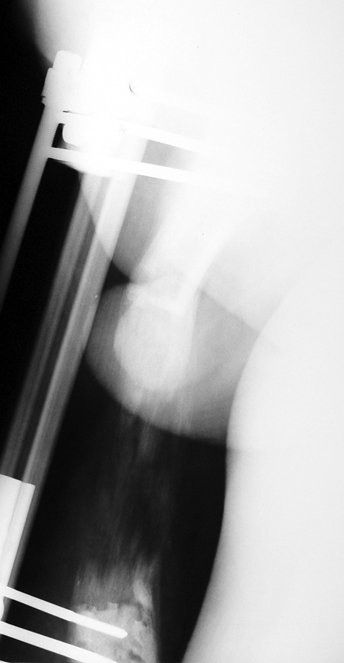

Vaka 1